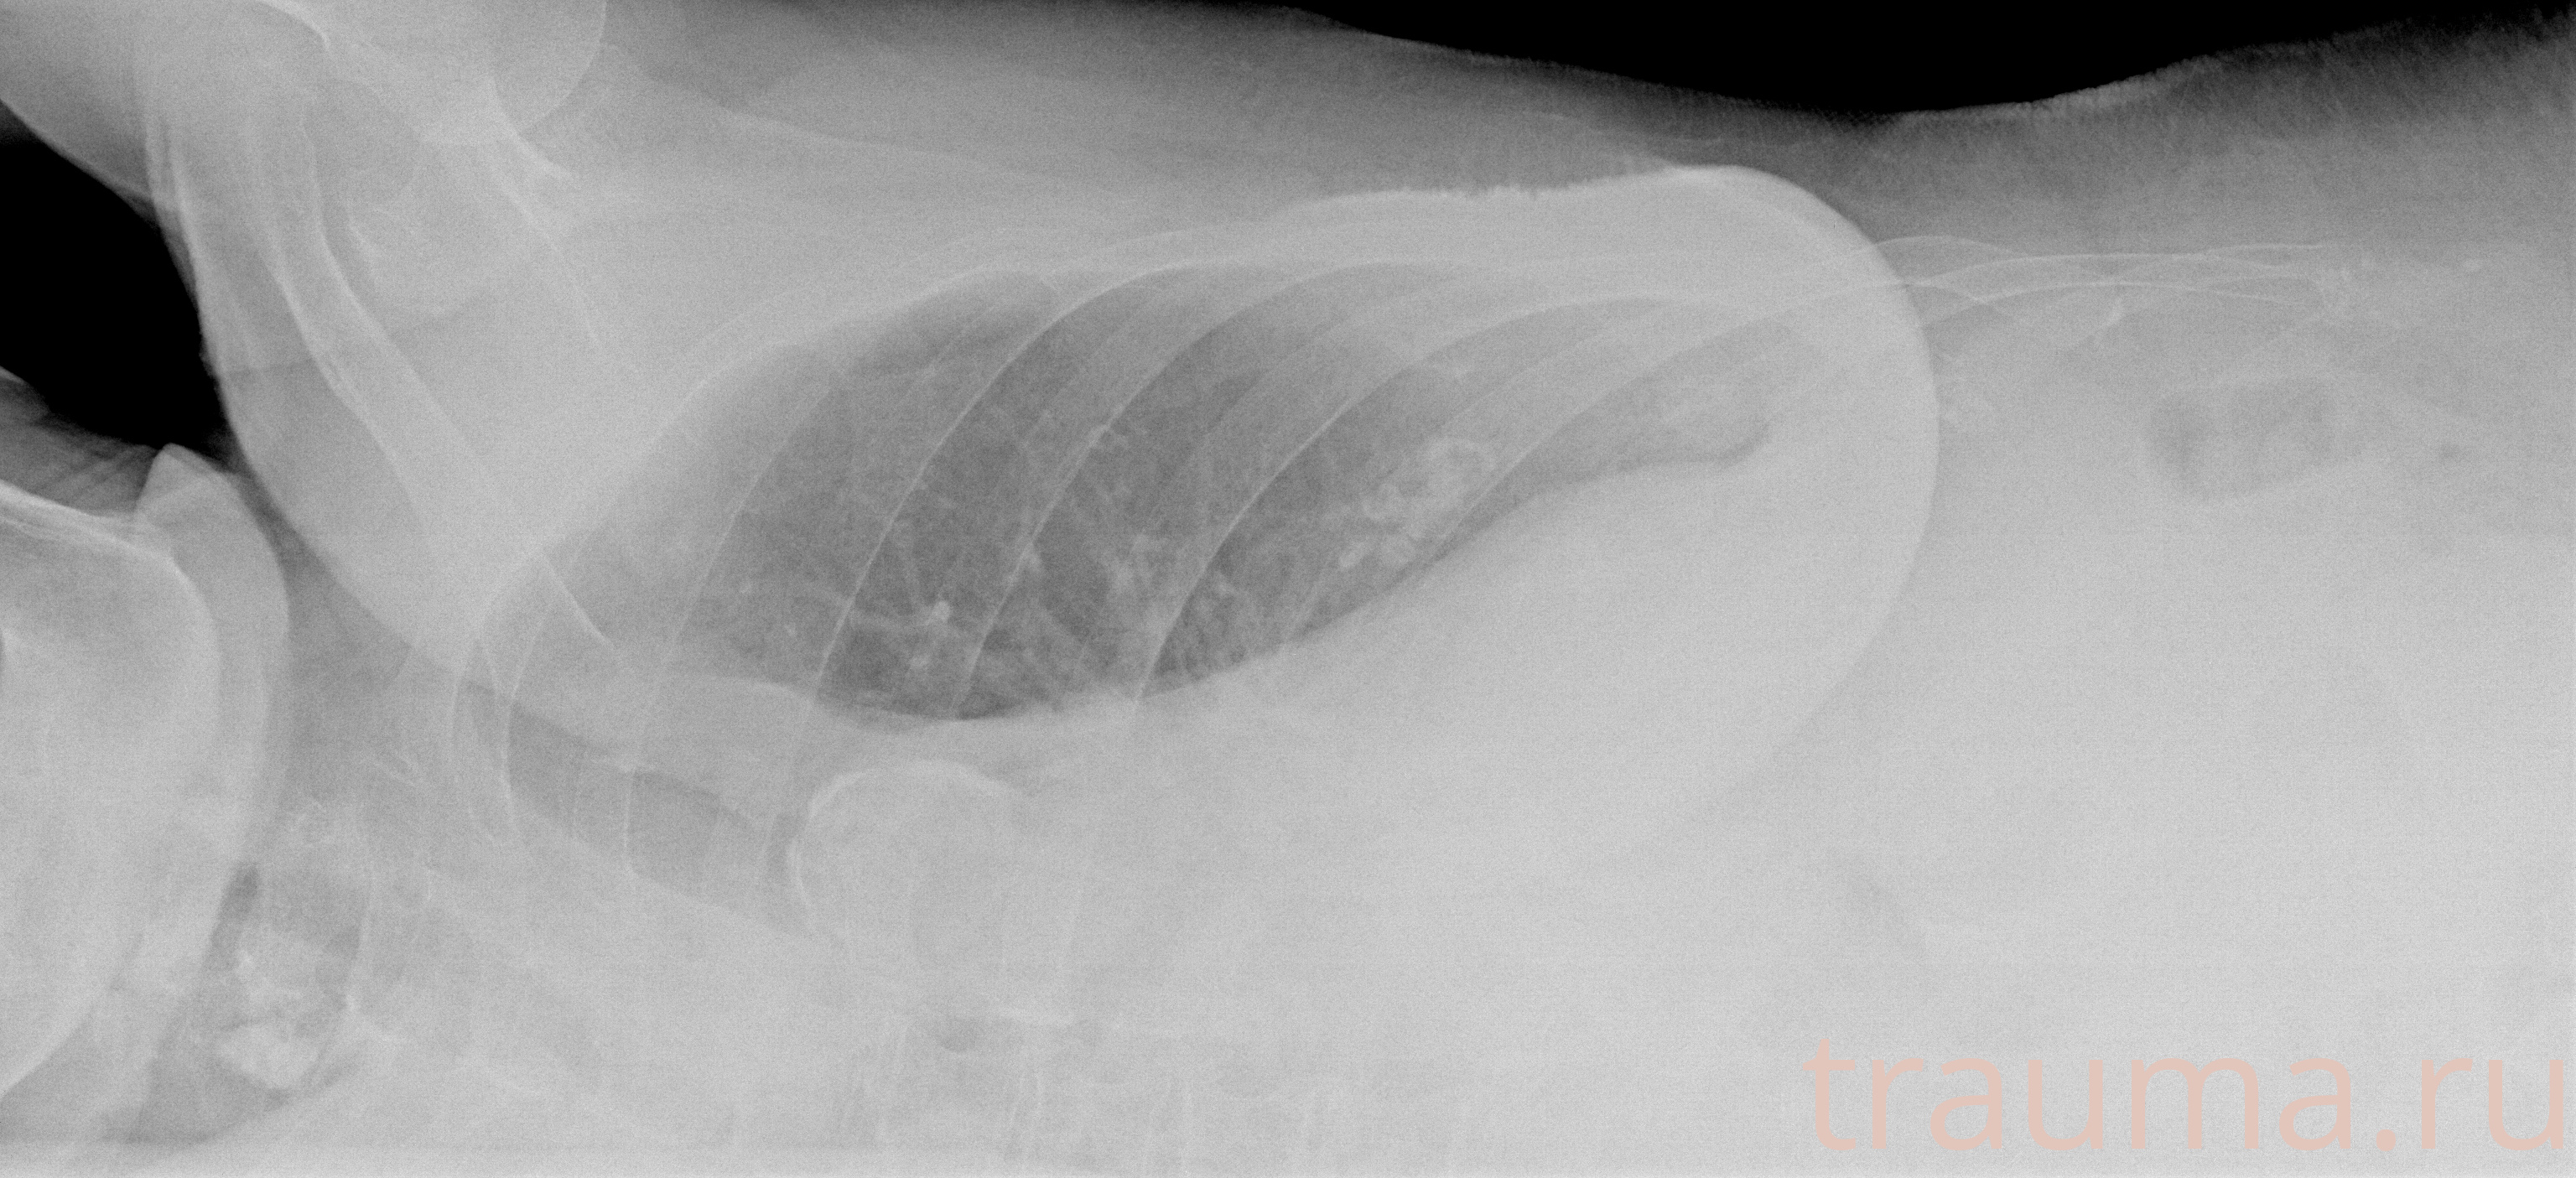

Рентген на дому: по вашему адресу приезжает врач-рентгенолог, травматолог-ортопед с мобильным рентгеновским аппаратом, проводит диагностику травмы или заболевания, делает необходимые рентгенограммы, дает рекомендации по дальнейшему лечению. Получить качественные снимки в домашних условиях возможно благодаря уникальной методике, разработанной МосРентген Центром для института  Склифосовского

при переломе шейки бедра и пневмонии от компании МосРентген Центр - партнера Института имени Склифосовского